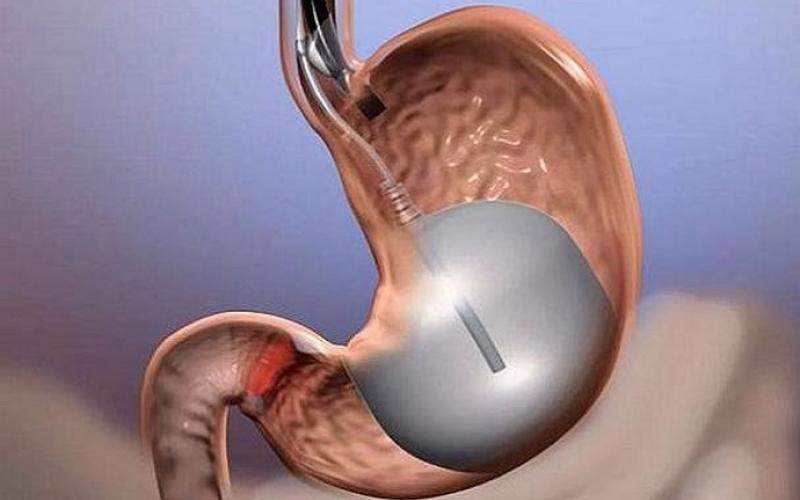

چاقی همچنین فاکتور پرخطر مستقل در ابتلا به بیماری کلیوی مزمن است. شیوه های مختلف درمان چاقی شامل تغییر در سبک زندگی، اصلاح رژیم غذایی، درمان به شیوه دارویی و جراحی است.

«آ شولمن»، سرپرست تیم تحقیق از دانشگاه گوتنبرگ سوئد، در این باره می گوید: «مطالعه ما تاثیرات بلندمدت جراحی برداشتن روده یا معده را به منظور کاهش وزن بر بیماری کلیوی نشان می دهد.»

نیمی از بیماران تحت جراحی کاهش وزن قرار گرفته و نیمی دیگر با شیوه های قراردادی غیرجراحی درمان شدند.